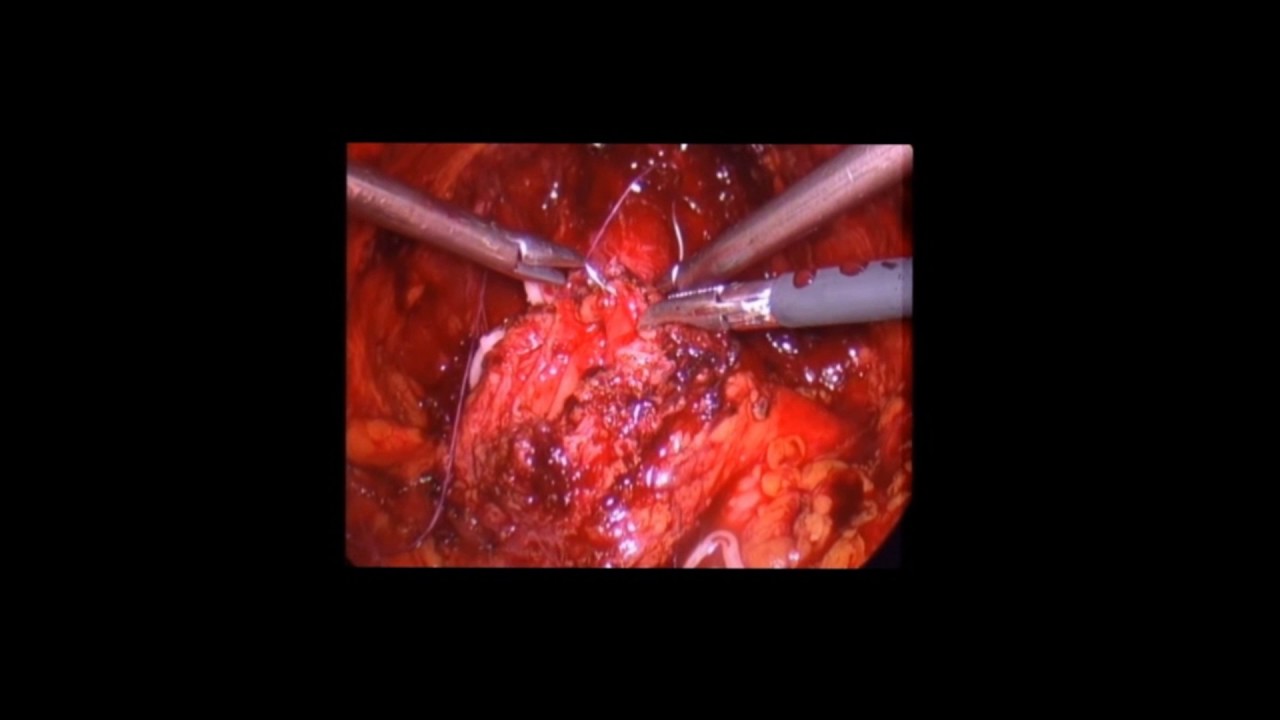

ESPECIALISTA CERTIFICADO ANTE EL CONSEJO NACIONAL MEXICANO DE UROLOGIA. Brindando la garantía y seguridad de que estas en manos de un profesional avalado a nivel nacional. CONOCIMIENTO DE LAS ÚLTIMAS TECNOLOGIAS. Ofeciendo las opciones mas novedosas y seguras de tratamiento. RELACIÓN DE CONFIANZA. Permitiendo que el paciente entienda por completo su enfermedad y pueda tomar las desiciones que lo lleven a recuperar su salud. SATISFACCIÓN DEL PACIENTE. Restaurarando la salud del paciente a costos accesibles es la mejor carta de presentación. EXPERIENCIA EN CIRUGÍA ENDOSCOPICA Y LAPAROSCOPICA. Opciones de mínima invasión que permiten una recuperación mas rapida y sin dolor, sin mencionar los resultados superiores esteticos respecto a la cirugía abierta. CIRUGÍA AMBULATORIA Y DE CORTA ESTANCIA. Las técnicas de mínima invasión y las ultimas tecnologías como el láser permiten que el paciente regrese a su casa y se reintegre a sus actividades cotidianas en pocas horas. PRESUPUESTOS EN BASE A SUS POSIBILIDADES ECONOMICAS. El éxito se mide en el numero de pacientes satisfechos, me ajusto a tu tabulador de gastos médicos y si no cuentas con uno te ofrezco presupuestos en base a tus recursos.

• Endourología y laparoscopia urológica